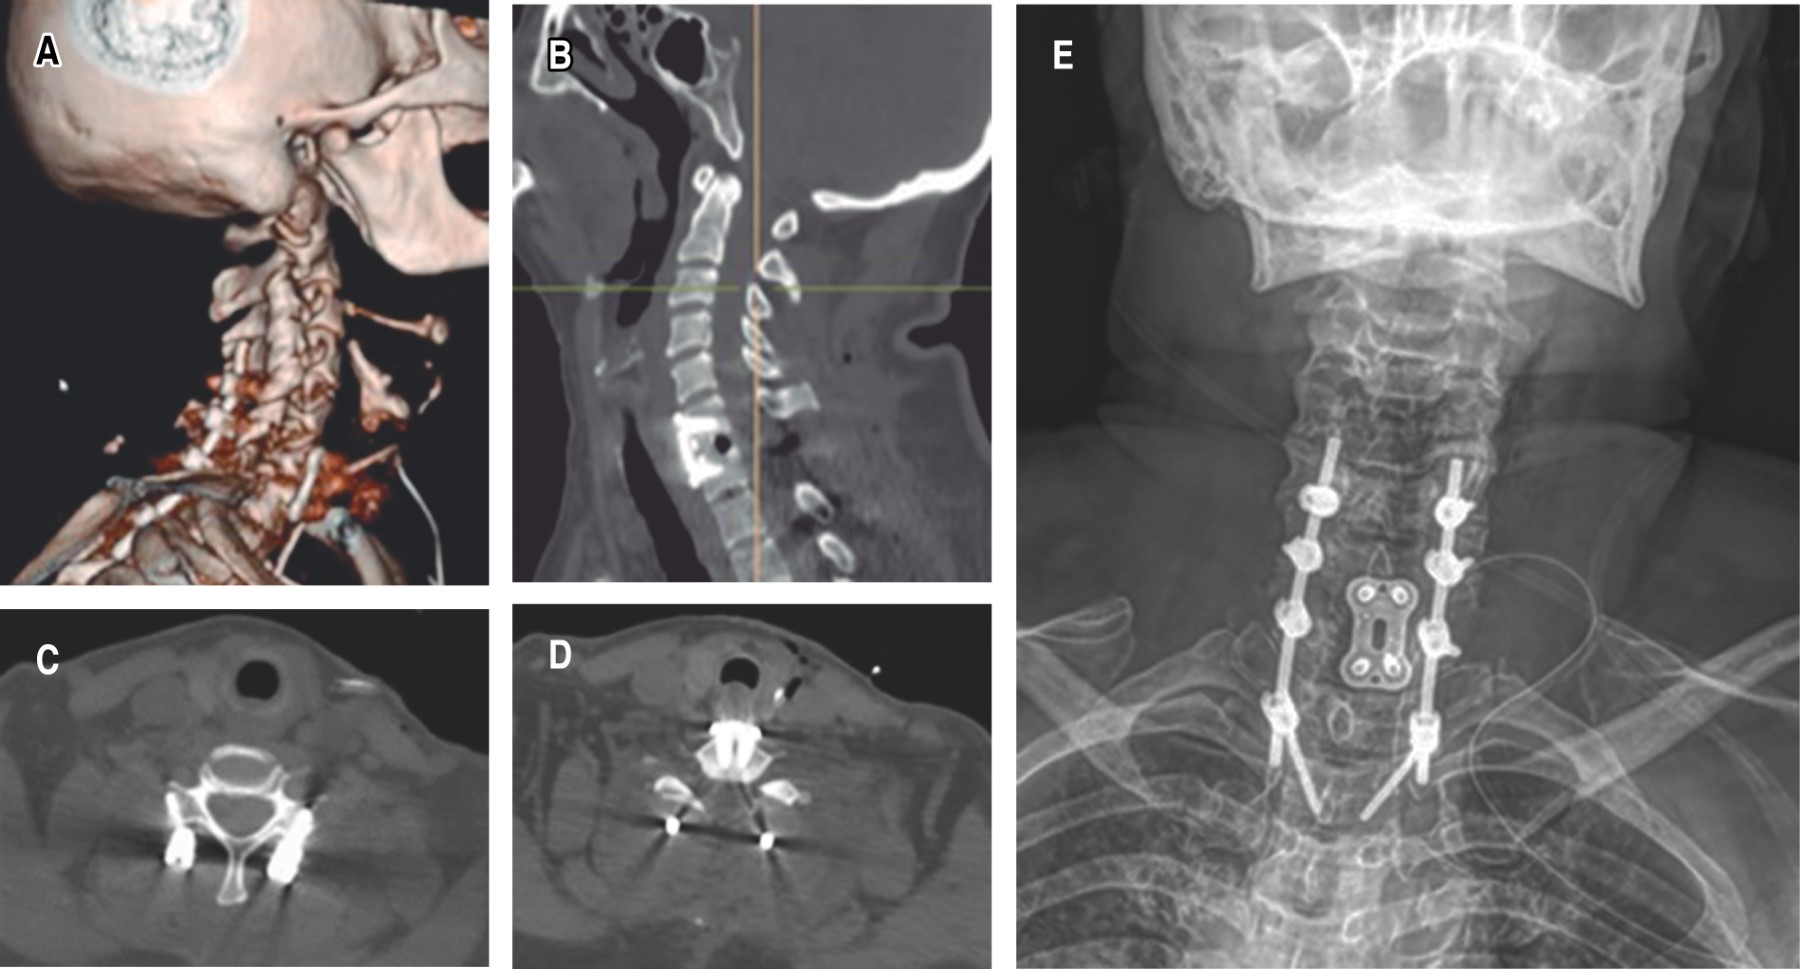

Posterior al interrogatorio y exploración física, se procede a solicitar estudios de gabinete con radiografías simples de columna cervical en proyecciones anteroposterior y lateral, así como tomografía axial computarizada, donde se observa desplazamiento anterior del cuerpo vertebral C5 sobre C6 e incongruencia articular facetaria mismos niveles. Se indica inmovilización con collarín rígido a permanencia en espera de realizar el complemento del estudio de imagen con una resonancia magnética nuclear simple de columna vertebral cervical corte sagital y axial T2 con presencia de compresión medular y lesión de complejo ligamentario posterior C5-C6. Se integra diagnóstico de luxación AO C5-C6:C (F4;N2;M1) ASIA D SLICS 5 y se procede a programar evento quirúrgico (Figura 1).

A los siete días después de su lesión, en primer orden se realiza el abordaje posterior con estabilización a masas laterales C4-C5 C5-C6, laminectomía C5-C6 y artrodesis posterolateral; se procede a efectuar un abordaje anterior con discectomía C5-C6 más fusión con caja intersomática tipo PEEK C5-C6 y placa anterior cervical, con una duración quirúrgica de tres horas 30 minutos para ambos abordajes y un sangrado reportado de 350 mililitros (Figura 2).